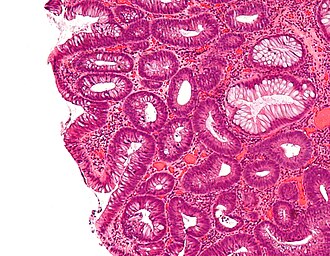

Tubular adenoma. H&E stain. | |

| LM | nuclear changes - esp. at the surface (hyperchromatic elongated nuclei or round cleared nuclei), nuclear crowding/pseudostratification, +/- loss of nuclear polarity, loss/decrease of goblet cells, cytoplasmic hyperchromasia |

| Subtypes | tubular adenoma, villous adenoma, tubulovillous adenoma |

- Nuclear changes at the surface of the mucosa - key feature.

- Size and shape or size change:

- Cigar-shaped (elongated) nucleus (usu. length:width > 3:1) with nuclear hyperchromasia (more blue).

- Large round nuclei +/- vesicular appearance (clearing) -- nuclei have white space.

- Nuclear crowding/pseudostratification - important.

- +/-Loss of nuclear polarity (nuclei no longer on basement membrane).

- Loss/decrease of goblet cells (common).

- Cytoplasmic hyperchromasia.